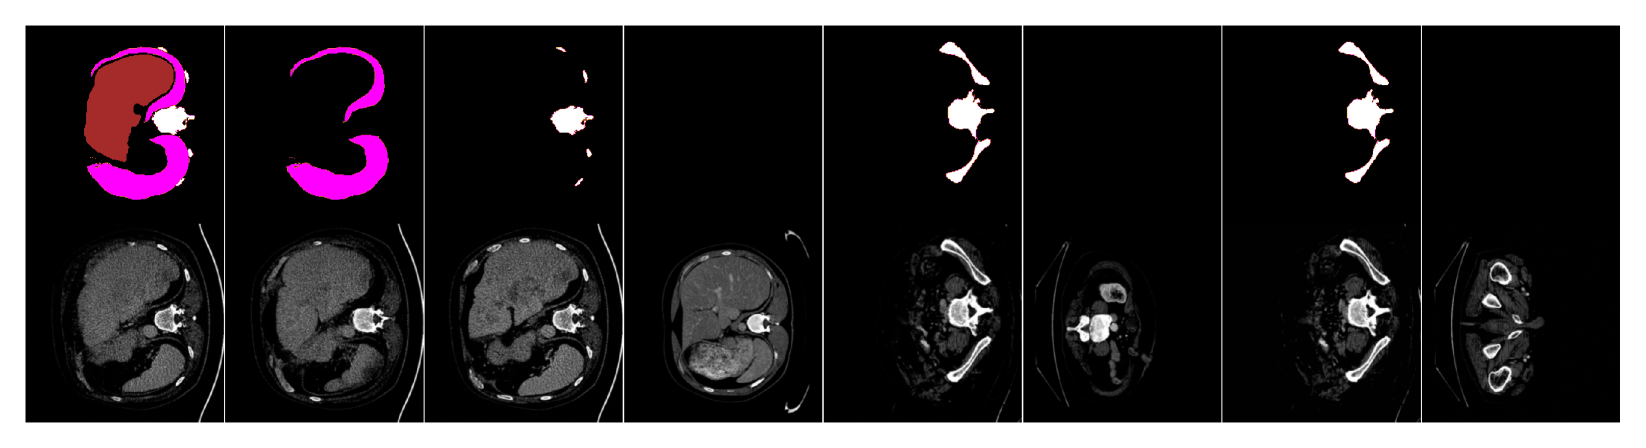

We will now compare our segmentation-guided diffusion model (“Seg-Diff” for short) to various state-of-the-art image generation models trained on each dataset: (1) the segmentation-conditional model ControlNet [Zhang et al.(2023)Zhang, Rao, and Agrawala], and the unconditional models of (2) a diffusion model identical to ours but trained without mask conditioning, and (3) StyleGAN2-ADA [Karras et al.(2020)Karras, Aittala, Hellsten, Laine, Lehtinen, and Aila], a state-of-the-art GAN model. We abbreviate these as CtrlNet, Unc-Diff and GAN, respectively, and training details for each are in Appendix A.2. We show exemplar generated images from all models in Fig. LABEL:fig:samples (more in Appendix D); for conditional models, input masks were randomly sampled from the test set.

fig:samples

This simple method generates images that are very faithful to input masks (Fig. LABEL:fig:samples), because the denoising process is conditioned on the mask at each of its many gradual steps, allowing the network to follow the masks because they provide helpful spatial information that is directly correlated with the optimal denoised model output that minimizes the loss.